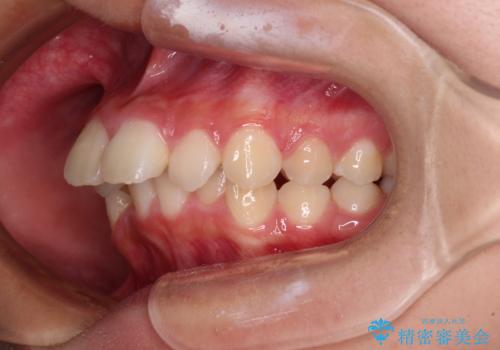

- 下唇の上に乗っかってしまうくらい前歯が飛び出していることを気にして来院された患者様です。

唇を閉じようとするとオトガイ部に力が入ってしまい、うまく閉じることができない状態であったため、上下左右の第一小臼歯4本を抜歯して、ワイヤー装置にて矯正治療を行うこととしました。

飛び出した前歯はしっかりと引っ込み、横顔の印象が大きく変化しました。